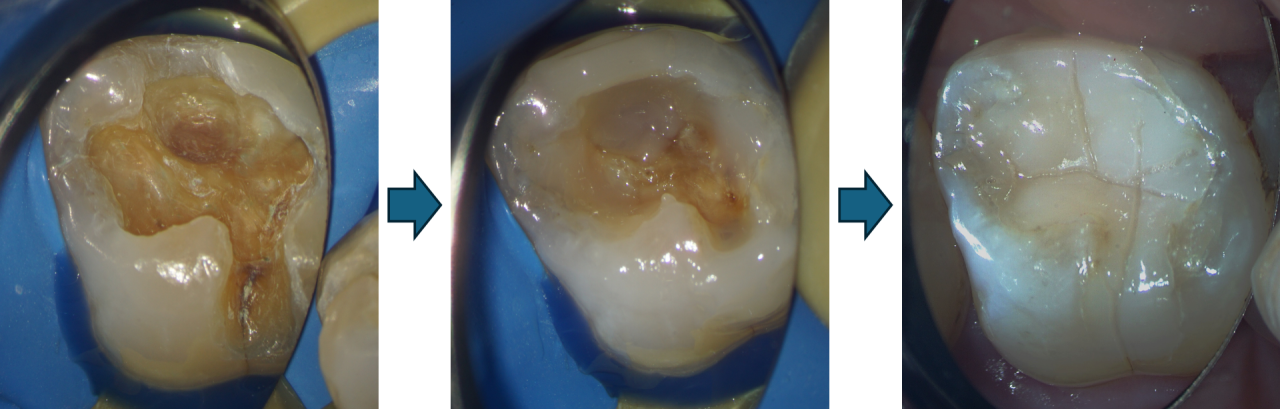

銀歯を外してみたところ、二次う蝕(詰め物の下で再発した虫歯)が確認できました。外からは分かりにくく、つめ物を外して初めて歯の状態がはっきりすることもあります。

虫歯を取り切って確認すると、歯に多くのヒビ割れが起きていました。銀歯が硬く歯を割りやすいために起きたものと考えられます。

実際の治療に戻ります。ラバーダムを行い、歯をしっかりと乾燥させ、レジンの接着を良くして、すき間やヒビ割れを起こりにくくします。

先ほど説明した積層充填を行います。一度にたくさんつめるのではなく、少しずつ(0.5mm~1.0mmずつ)レジンをつめて、歯への負担をできるだけ最小限になるようにします。

十回以上少しずつつめていき、きれいにつめ終わりました。